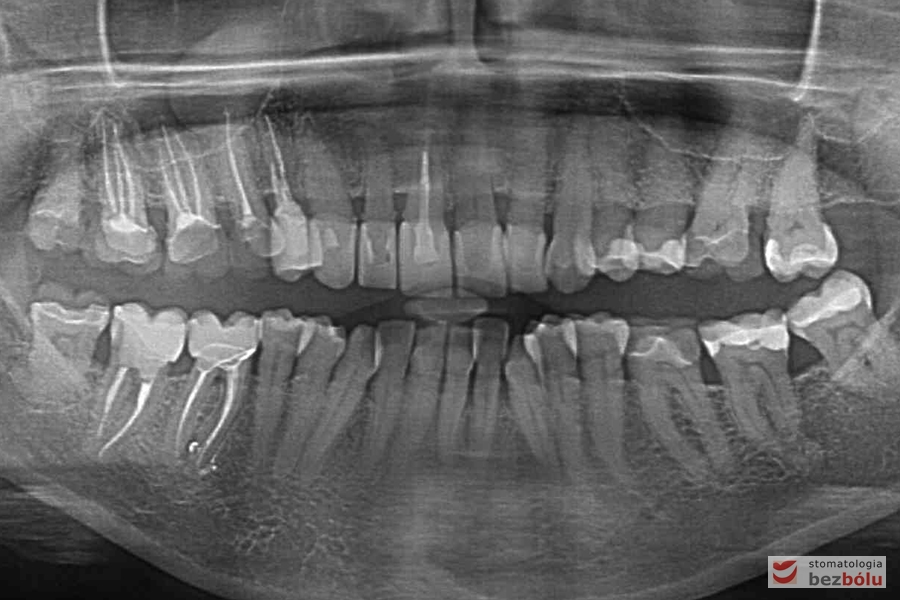

Kontrola radiologiczna - liczne zęby z niekompletną endodoncją, ubytek kości w szczęce

Kontrola radiologiczna – liczne zęby z niekompletną endodoncją, ubytek kości w szczęce